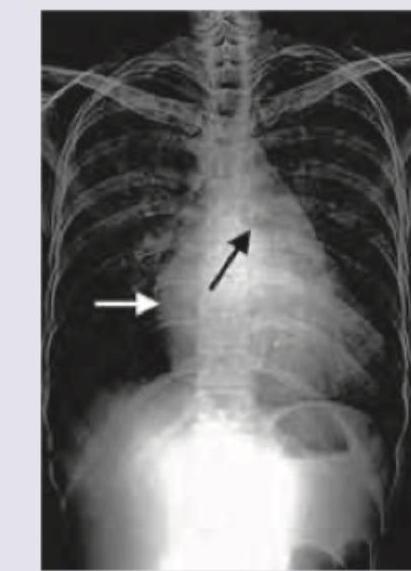

A 16-year-old boy is admitted with rapidly accumulating bilateral pleural effusion. His chest X-ray is shown below. Which of the following is incorrect about the X-ray shown?

Explanation: ***Pneumothorax*** - A **pneumothorax** is characterized by the presence of **air in the pleural space**, which typically appears as a **lucent area** without lung markings and a displaced visceral pleural line on X-ray. - The presented chest X-ray shows **dense opacities at the lung bases**, consistent with fluid accumulation (**pleural effusion**), not air. *Left-sided pleural effusion* - The image clearly shows significant **opacification of the left hemithorax** with blunting of the **costophrenic angle** and obscuring of the left hemidiaphragm. - This finding is consistent with a large amount of fluid, indicating a **left-sided pleural effusion**. *Mediastinum shifted to right* - The **trachea** and **cardiac silhouette** are visibly displaced towards the **right side** of the chest. - This shift is a consequence of the large **left-sided pleural effusion exerting mass effect** and pushing the mediastinal structures away from the affected side. *Bilateral ICD tubes* - There are discernable radiopaque lines extending into both pleural spaces, representing **bilateral intercostal drainage (ICD) tubes**. - These tubes are placed to drain the **accumulated pleural fluid** from both the right and left sides.